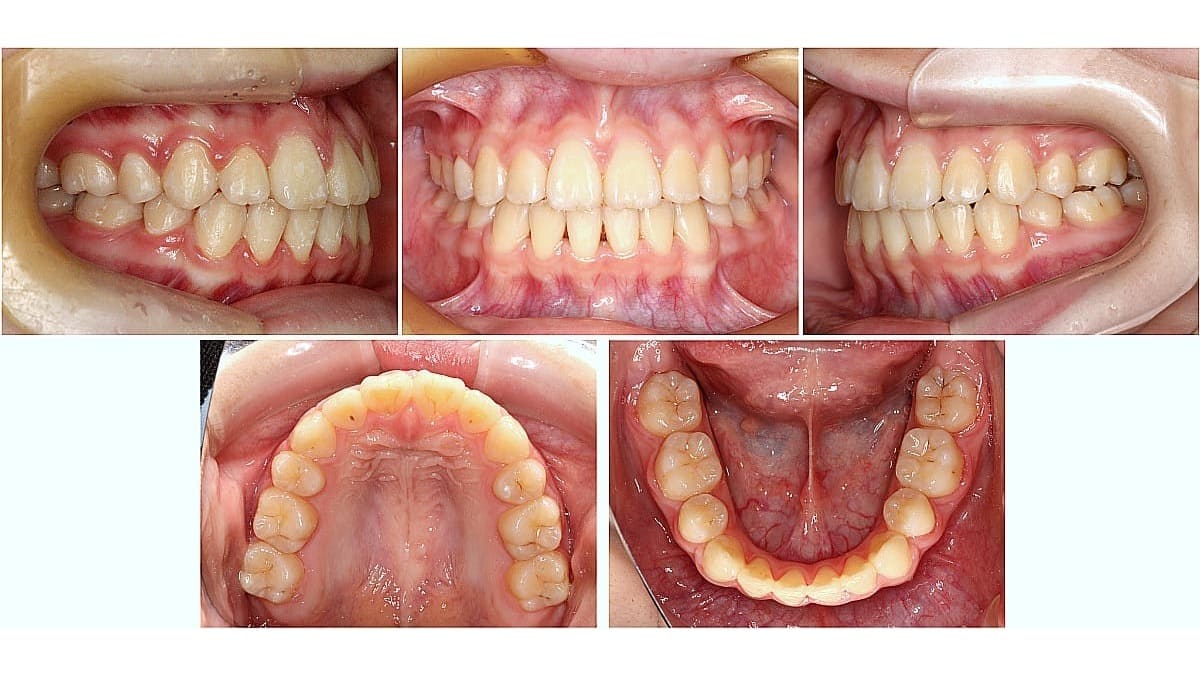

| 主訴 | 歯がガタガタ |

| 治療内容 | マルチブラケット |

| 治療期間 | 2年1ヶ月 |

| 費用 | 850,000円(税込) |

| 治療のリスク | 歯根吸収、歯肉退縮、歯髄失活 |